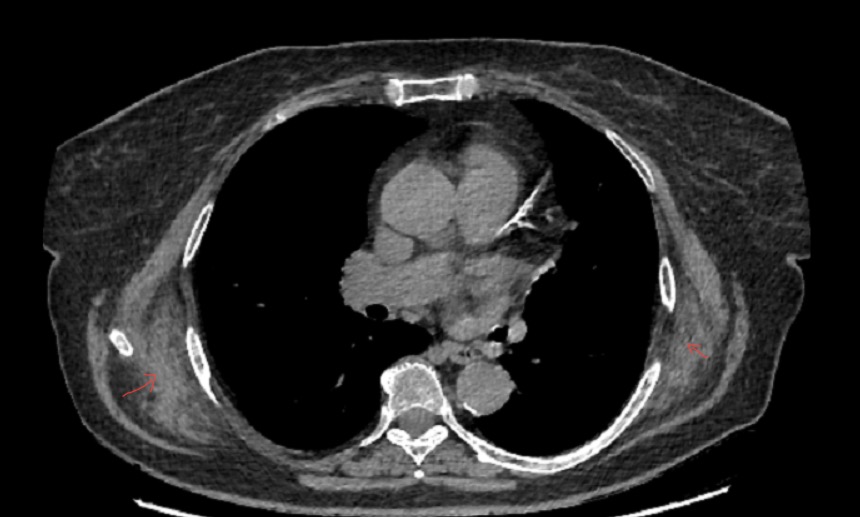

Computed tomography findings may be highly suggestive of this pathology, most commonly showing a poorly defined soft-tissue mass with attenuation similar to the adjacent skeletal muscle and having internal striations or scattered areas of fat. Studies show that the smaller the tumor, the more homogenous attenuation will show on a computed tomography scan.5

Similar characteristics have been shown on our patient’s computed tomography scan; the tumors were situated posterior to the serratus muscles and anterior to the latissimus dorsi and scapular plane (Figures 1 and 2).

Figure 1. Computed tomography scan of the patient showing the 2 tumors situated anterior to the scapular plane.

Figure 2. Computed tomography scan from an anterior and lateral perspective.